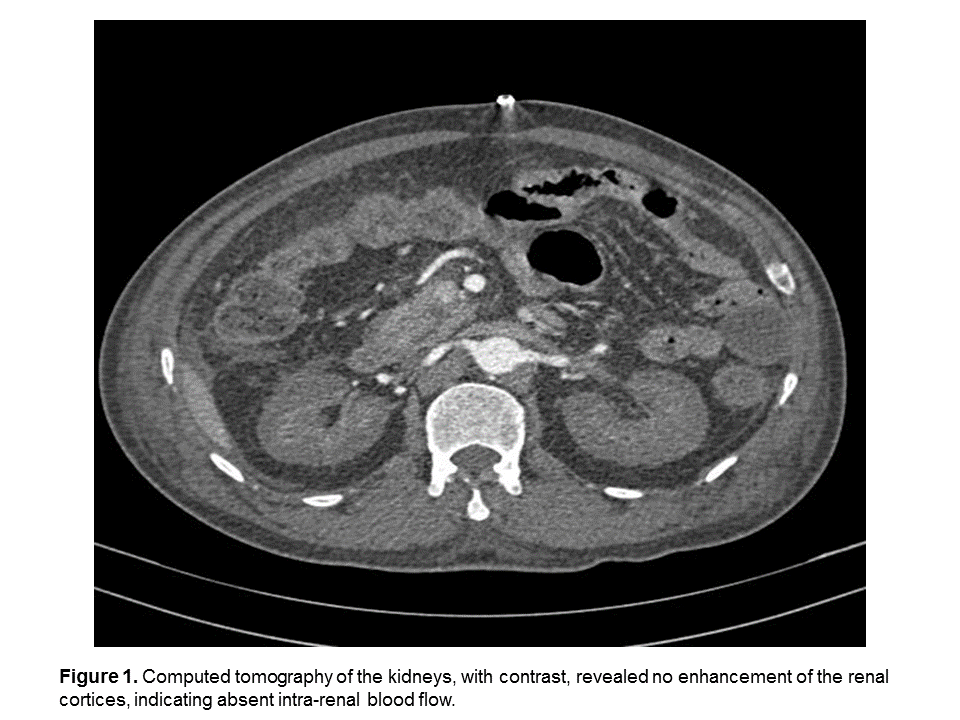

A 58-year-old patient developed complete anuria following elective abdominal surgery for an ileocaecal mass. Contrast-enhanced computed tomography demonstrated absent intra-renal blood flow and a kidney biopsy confirmed diffuse cortical necrosis. Histology of the ileocaecal mas displayed deep fissuring which was diagnostic of Crohn’s disease. Bilateral renal cortical necrosis (BRCN) is a rare complication of surgery but should be considered in any patient developing complete anuria. Since the disease is often associated with a coagulopathy, conditions predisposing to thrombosis should be sought. Inflammatory Bowel Disease (IBD) with surgical complications, as in this case, should be considered among the conditions which may predispose to BRCN.